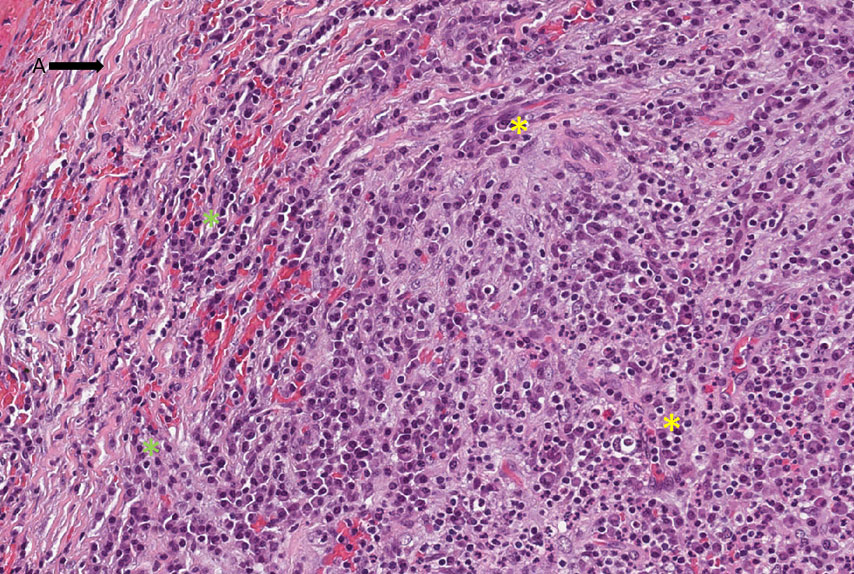

Cavidade (lúmen) contendo piócitos (pus), tecido conjuntivo contendo neutrófilos, infiltrado inflamatório linfoplasmocitário (asterisco amarelo) e vasos de neoformação, externamente cápsula fibrosa, caracterizando tecido de granulação. (Figura 1)

Observar a cavidade virtual, contendo pus (piócitos — Figura 2 — área tracejada em preto e setas), circundada por tecido de granulação apresentando infiltrado inflamatório contendo plasmócitos (asterisco amarelo-Figura 3) linfócitos (asterisco verde), neoformação vascular e fibroplasia (seta A — Figura 3). Na periferia observa-se uma maior deposição de fibras colágenas caracterizando uma cápsula fibrosa.

Tecido conjuntivo denso exibindo uma resposta crônica com infiltrado inflamatório predominantemente de linfócitos (asterisco amarelo) e plasmócitos (asterisco verde), vasos de neoformação (setas amarelas) e fibras colágenas. .